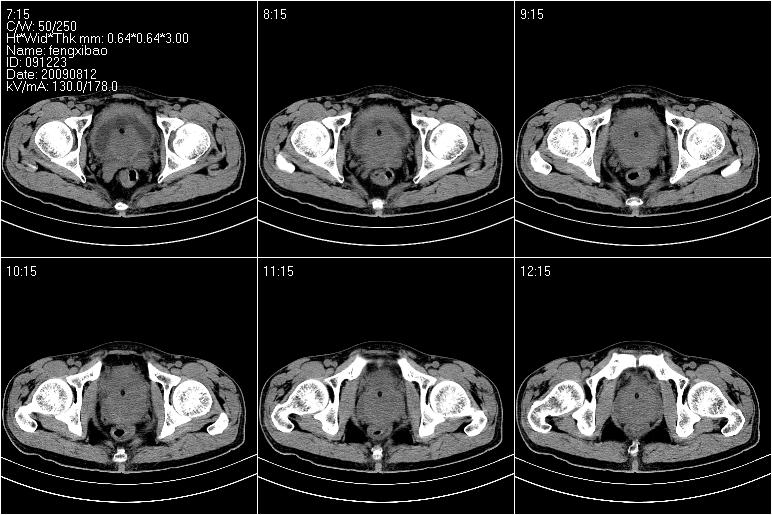

标题: CT21568:男,57岁,双肾及输尿管重度积水。彩超示前列腺占 [打印本页]

标题: CT21568:男,57岁,双肾及输尿管重度积水。彩超示前列腺占

考虑前列腺增生并慢性尿潴留致膀胱肌小梁增生

考虑膀胱癌侵犯双侧输尿管末端及前列腺,双输尿管扩张积水。

前列腺增生肥大,内密度不均,ca不排外;膀胱壁弥漫性增厚,膀胱精囊三角清,炎症?

前列腺ca;膀胱炎,膀胱、直肠受累不除外

考虑膀胱癌侵犯双侧输尿管末端及前列腺,双输尿管扩张积水.

1 前列腺增生肥大,不除外癌变可能,建议mr检查

2 膀胱壁弥漫性增厚,内侧可见增粗的小梁和腺体,考虑为腺性膀胱炎

前列腺增生,内密度不均,警惕癌变,膀胱壁弥漫性增厚,考虑慢性膀胱炎。

考虑前列腺增生症并腺性膀胱炎,双侧输尿管扩张;建议必要时行mri检查。

1、前列腺改变主要为中央区,考虑前列腺增生可能性大。

2、膀胱壁弥漫性增厚,考虑膀胱炎可能,请结合临床。

考虑前列腺增生并慢性膀胱炎。不除外前列腺癌可能。建议结合其它检查。

考虑:前列腺增生并慢性膀胱炎。不除外前列腺癌可能。建议结合其它检查。